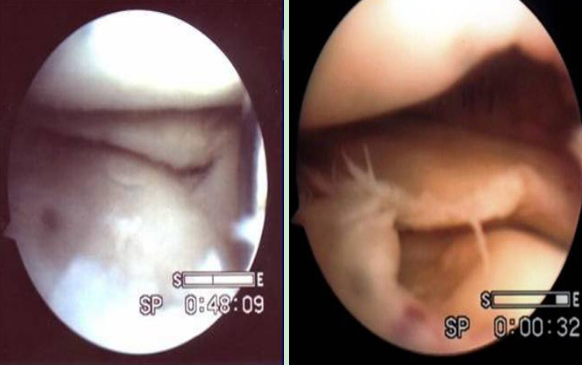

縱裂

桶柄裂

橫裂

瓣裂

不規(guī)則裂